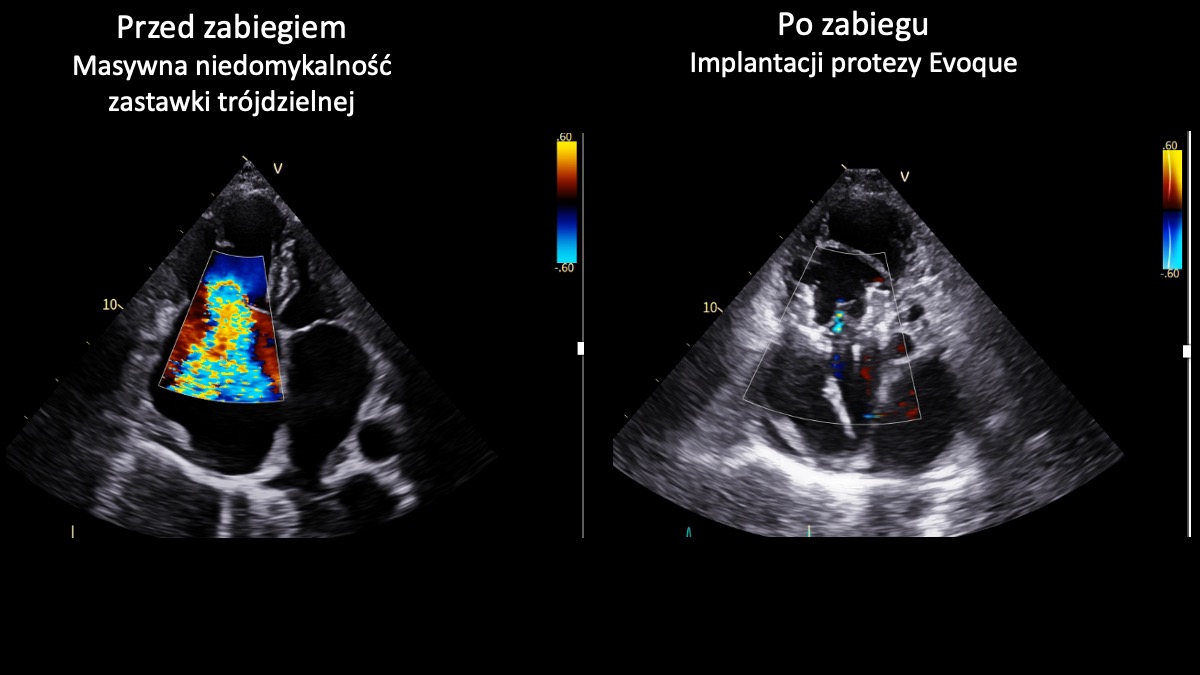

Zespół I Kliniki Kardiologii UCK GUMed, kierowanej przez prof. Marcina Gruchałę,  z powodzeniem przeprowadził dwa nowatorskie zabiegi przezcewnikowej implantacji zastawki trójdzielnej Evoque z wykorzystaniem wizualizacji 3D. Te wyjątkowe – także w skali światowej – operacje są odpowiedzią na brak innej terapii dla pacjentów z niewydolnością serca spowodowanej masywną niedomykalnością zastawki trójdzielnej. – Zabiegi tego typu należą do najbardziej zaawansowanych w kardiologii interwencyjnej – podkreśla prof. Fijałkowski.

Zastawka trójdzielna znajduje się w prawej części serca i działa jak „zawór”, który zapewnia prawidłowy przepływ krwi w jednym kierunku. W przypadku niedomykalności nie zamyka się szczelnie, przez co część krwi cofa się, zamiast płynąć dalej. Masywna niedomykalność oznacza bardzo zaawansowaną postać tej wady – cofanie krwi jest znaczne, co prowadzi do przeciążenia serca i objawów takich jak: duszność, szybkie męczenie się czy obrzęki nóg. Nieleczona może prowadzić do poważnego pogorszenia jakości życia i niewydolności serca, a w konsekwencji – do śmierci.

- Obie przeprowadzone implantacje zastawki trójdzielnej Evoque zakończyły się sukcesem. To ważny krok w rozwoju małoinwazyjnego leczenia pacjentów z  zaawansowanymi wadami zastawkowymi. Dla chorych obciążonych bardzo wysokim ryzykiem operacyjnym i bez innych realnych możliwości leczenia to obecnie jedyna szansa na skuteczną terapię - podkreśla prof. Marcin Fijałkowski. – Zabiegi tego typu należą nadal do najbardziej zaawansowanych procedur w kardiologii interwencyjnej. Wykonując je w UCK, dołączyliśmy do wąskiego grona ośrodków europejskich oferujących pełne spektrum przezcewnikowego leczenia chorób strukturalnych serca, w tym wad zastawkowych – dodaje.

Zabiegi wykonano u dwóch 80-letnich pacjentek. Pierwszy z nich był monitorowany z wykorzystaniem nowoczesnego systemu echokardiograficznego GE HealthCare Vivid Pioneer, który umożliwia obrazowanie struktur serca w czasie rzeczywistym w technologii 3D. Drugą procedurę wspomagała sonda wewnątrzsercowa Philips VeriSight Pro 3D ICE, pozwalająca na wyjątkowo precyzyjną wizualizację serca podczas zabiegu. Zastosowanie tych technologii czyni przeprowadzone procedury nowatorskimi również w skali światowej. Tego typu zabiegi stanowią przyszłość kardiologii i wyznaczają kierunek dalszego rozwoju leczenia zaawansowanych chorób serca. Obie chore opuściły już szpital w stanie znacznej poprawy.